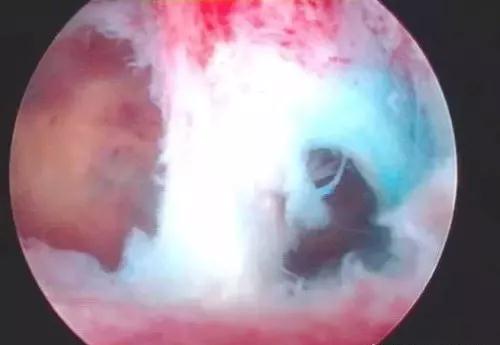

宫腔镜是通过一个微型的镜头进入子宫腔,观察宫腔环境,明确宫腔粘连的位置与范围程度。

如果是轻度或轻到中度的粘连,是可以直接在宫腔镜下进行粘连分解的。

如果较为严重的粘连患者,可能需要之后分多次的宫腔镜手术。在第一次粘连分解之后,我们需要用一些药物去序贯治疗,也会在宫腔内放入支架或节育环,在节育环上放置防粘连的生物材料。

宁波送子鸟专家提示:坚持如上原则做到宫腔镜下子宫恢复正常或大致正常宫腔解剖形态并不困难,进一步恢复月经,防止再粘连,促进内膜修复和增生以及提高妊娠率。